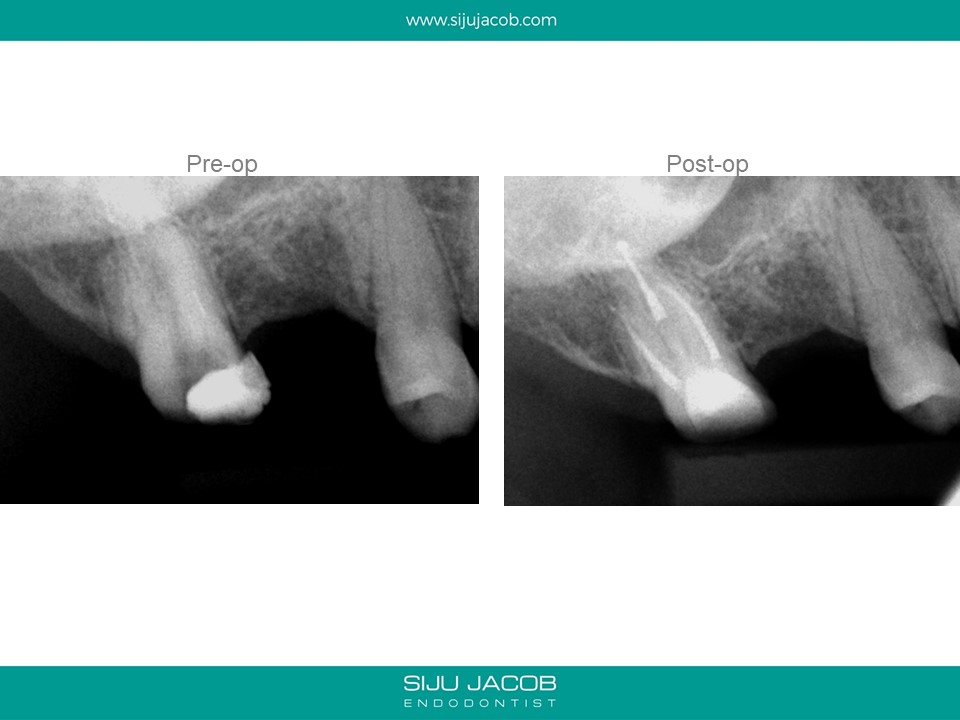

The previous practitioner fractured an instrument in the mesio-buccal root and referred this case. Instrument retrieval is usually fast and quite predictable in locations like the middle and coronal thirds.